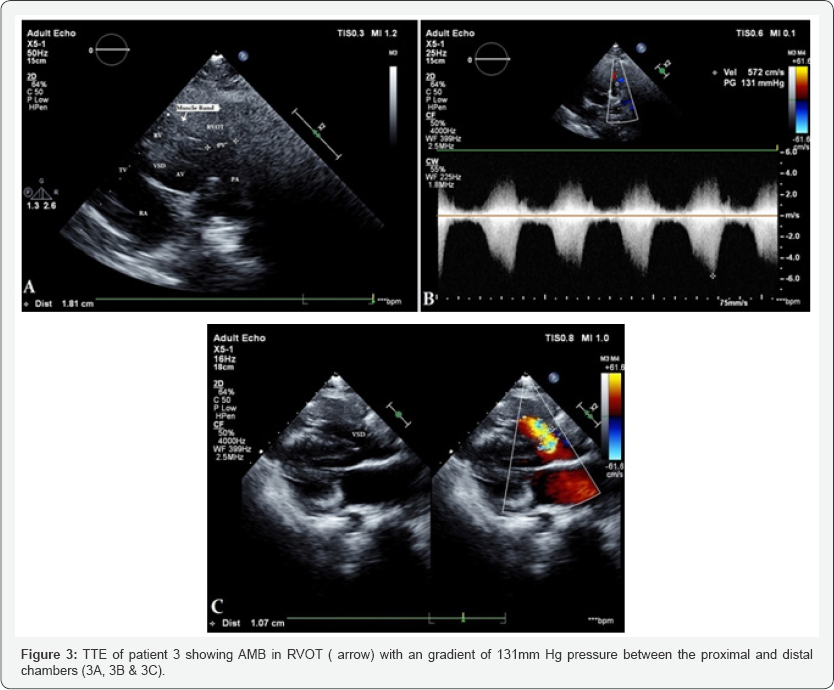

All patients underwent detailed echocardiography, pulmonic valve was normal in all patients. Cardiac catheterization and catheterization was done in all patients, Figure 1 showing cath of Patient 1. Figure 1-3 showing echo findings of patient 1, 2 & 3. Echocardiography and catheterization findings are shown in Table 2.